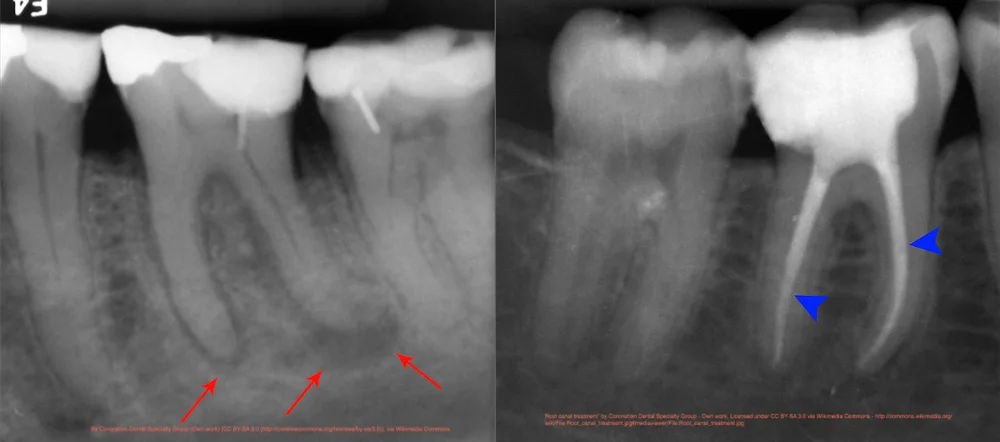

Based on your location our. Root Canal Treatment aka Endodontics is available at Amber Vet for pet owners who want to save their pets teeth that are functionally important such as Canine fang teeth and Chewing. In this procedure the endodontist opens the gum tissue near the tooth to see the underlying bone and to remove any inflamed or infected tissue.

Utilising The Anatomy In Molar Root Canal Retreatment Dentistry Online